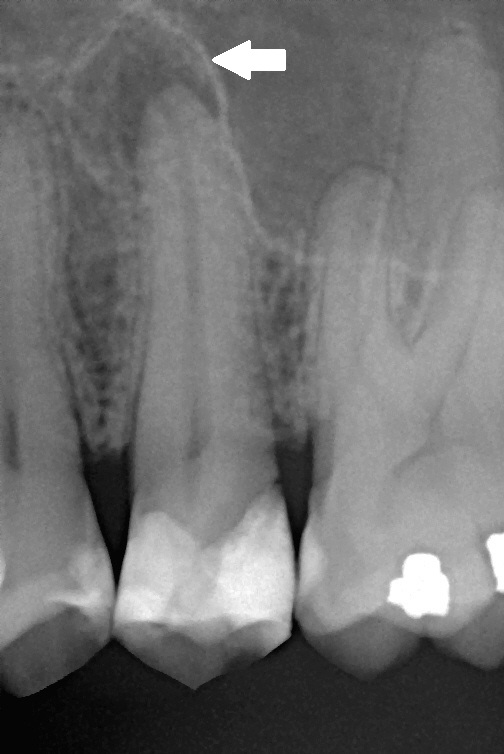

The response leads to gums becoming inflamed which causes them to bleed and detach from the tooth forming “pockets”. The plaque then grows into these pockets below the gum level. Once under the gum, brushing and flossing will not remove it.

Over time, the pockets increase in depth and the bone around the teeth is destroyed, while the gums recede. Eventually, if left untreated, the tooth will be lost.